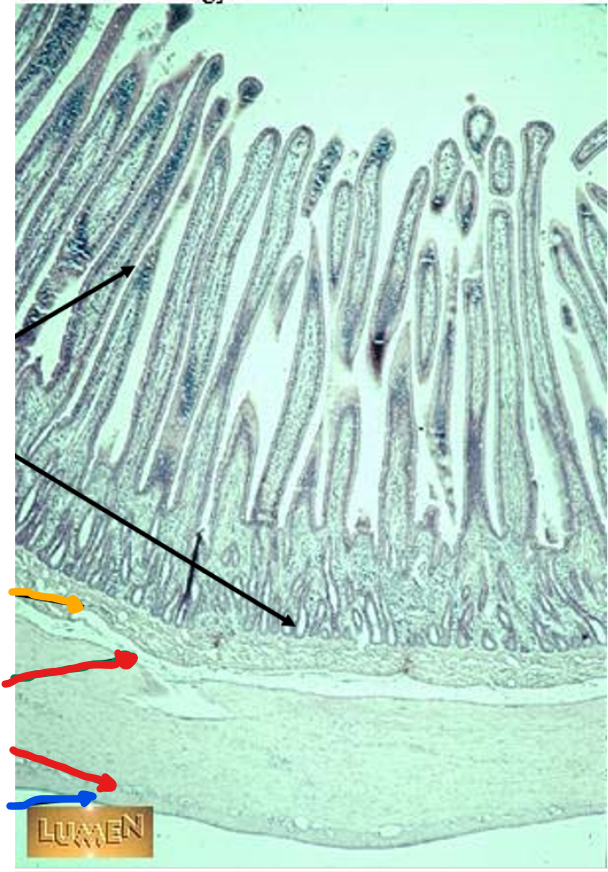

plicae circulares

green

villi

crypts

blue

lamina propria

black

simple columnar epithelium

the blue arrow

the red arrow

the black arrows

this is in the

jejunum

black arrows

mucosa

yellow arrow

submucosa

red arrows

muscularis externa

blue arrow

serosa